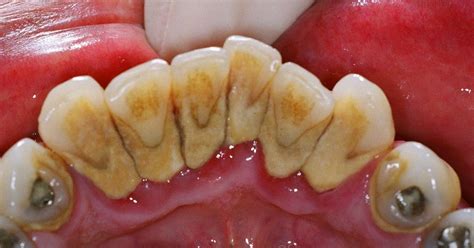

A diferencia de la placa que es una película incolora, el sarro presenta minerales siendo fácilmente visible si se localiza por encima de la línea de las encías. El indicador de sarro más común es observar un color marrón o amarillento en los dientes o encías. En general, el dentista puede detectar la presencia de sarro a simple vista mediante una exploración.

El sarro duro detrás de los dientes presenta inicialmente una coloración amarillenta que puede evolucionar hacia tonos marrones o incluso negros, dependiendo de factores como el tabaquismo, el consumo de té, café o ciertos alimentos.

La anatomía oral explica por qué el sarro duro detrás de los dientes inferiores es tan común. Las glándulas sublinguales y submandibulares, ubicadas debajo de la lengua, secretan constantemente saliva rica en minerales directamente hacia la superficie lingual de los incisivos inferiores. La superficie lingual de los dientes inferiores representa una de las zonas más desafiantes para mantener una higiene bucal adecuada.

La posición de la lengua, la limitada visibilidad durante el cepillado y la dificultad para maniobrar el cepillo en esta área contribuyen a una limpieza incompleta. Muchas personas concentran sus esfuerzos de higiene bucal en las superficies dentales más visibles, descuidando inadvertidamente las zonas posteriores y linguales.